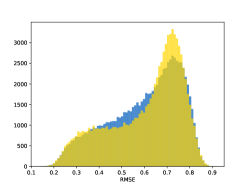

To visualise similarity metrics that compare image pairs (RMSE, SRE, SSIM) two metric distributions are generated: intra-similarity and inter-similarity. For each compared sample 300 random images are selected. The inter-similarity distribution is calculated for each image pair combination from both compared samples e.g. generated images of COVID-19 and real images of COVID-19. For the intra-similarity, all pairs of images in a single sample e.g real images of COVID-19 are considered. By comparing the shape of intra-similarity for the training subsample (Dataset) with the inter-similarity of training and generated samples the quality of the generated sample can be judged. It is also possible to compare in this way between the four image classes present in the dataset. The resulting distributions of inter-similarity of COVID-19 and the three remaining classes are compared in Fig. 4 to distributions of intra-similarity of the COVID-19 sample for each metric. All metrics, as expected based on available medical evidence Rubin et al. (2020), indicate that there are visible differences not only between COVID-19 and normal samples but also between viral pneumonia and lung opacity. Therefore, all classes should be distinguishable.

To visualise differences between synthetic and real samples distributions are generated for each of the RMSE, SRE and SSIM metrics: intra-similarity and inter-similarity. For each compared sample 300 random images are selected. The inter-similarity distribution is calculated for each image pair combination from both compared samples e.g. generated images of COVID-19 and real images of COVID-19. For the intra-similarity, all pairs of images in a single sample e.g real images of COVID-19 are considered. The distributions for generated samples describe very well the distributions for corresponding real images as shown in Fig. 6.

The quality of generated images is also confirmed with classical similarity metrics. The distributions of those similarity measures between generated and real images are compared for each sample with the distribution obtained within the real samples 6. The distributions for generated samples describe very well the distributions for corresponding real images. For an example see the results for the SSIM metric presented in Fig. 10. The small visible differences are almost insignificant compared to differences observed between the classes in Fig. 4.